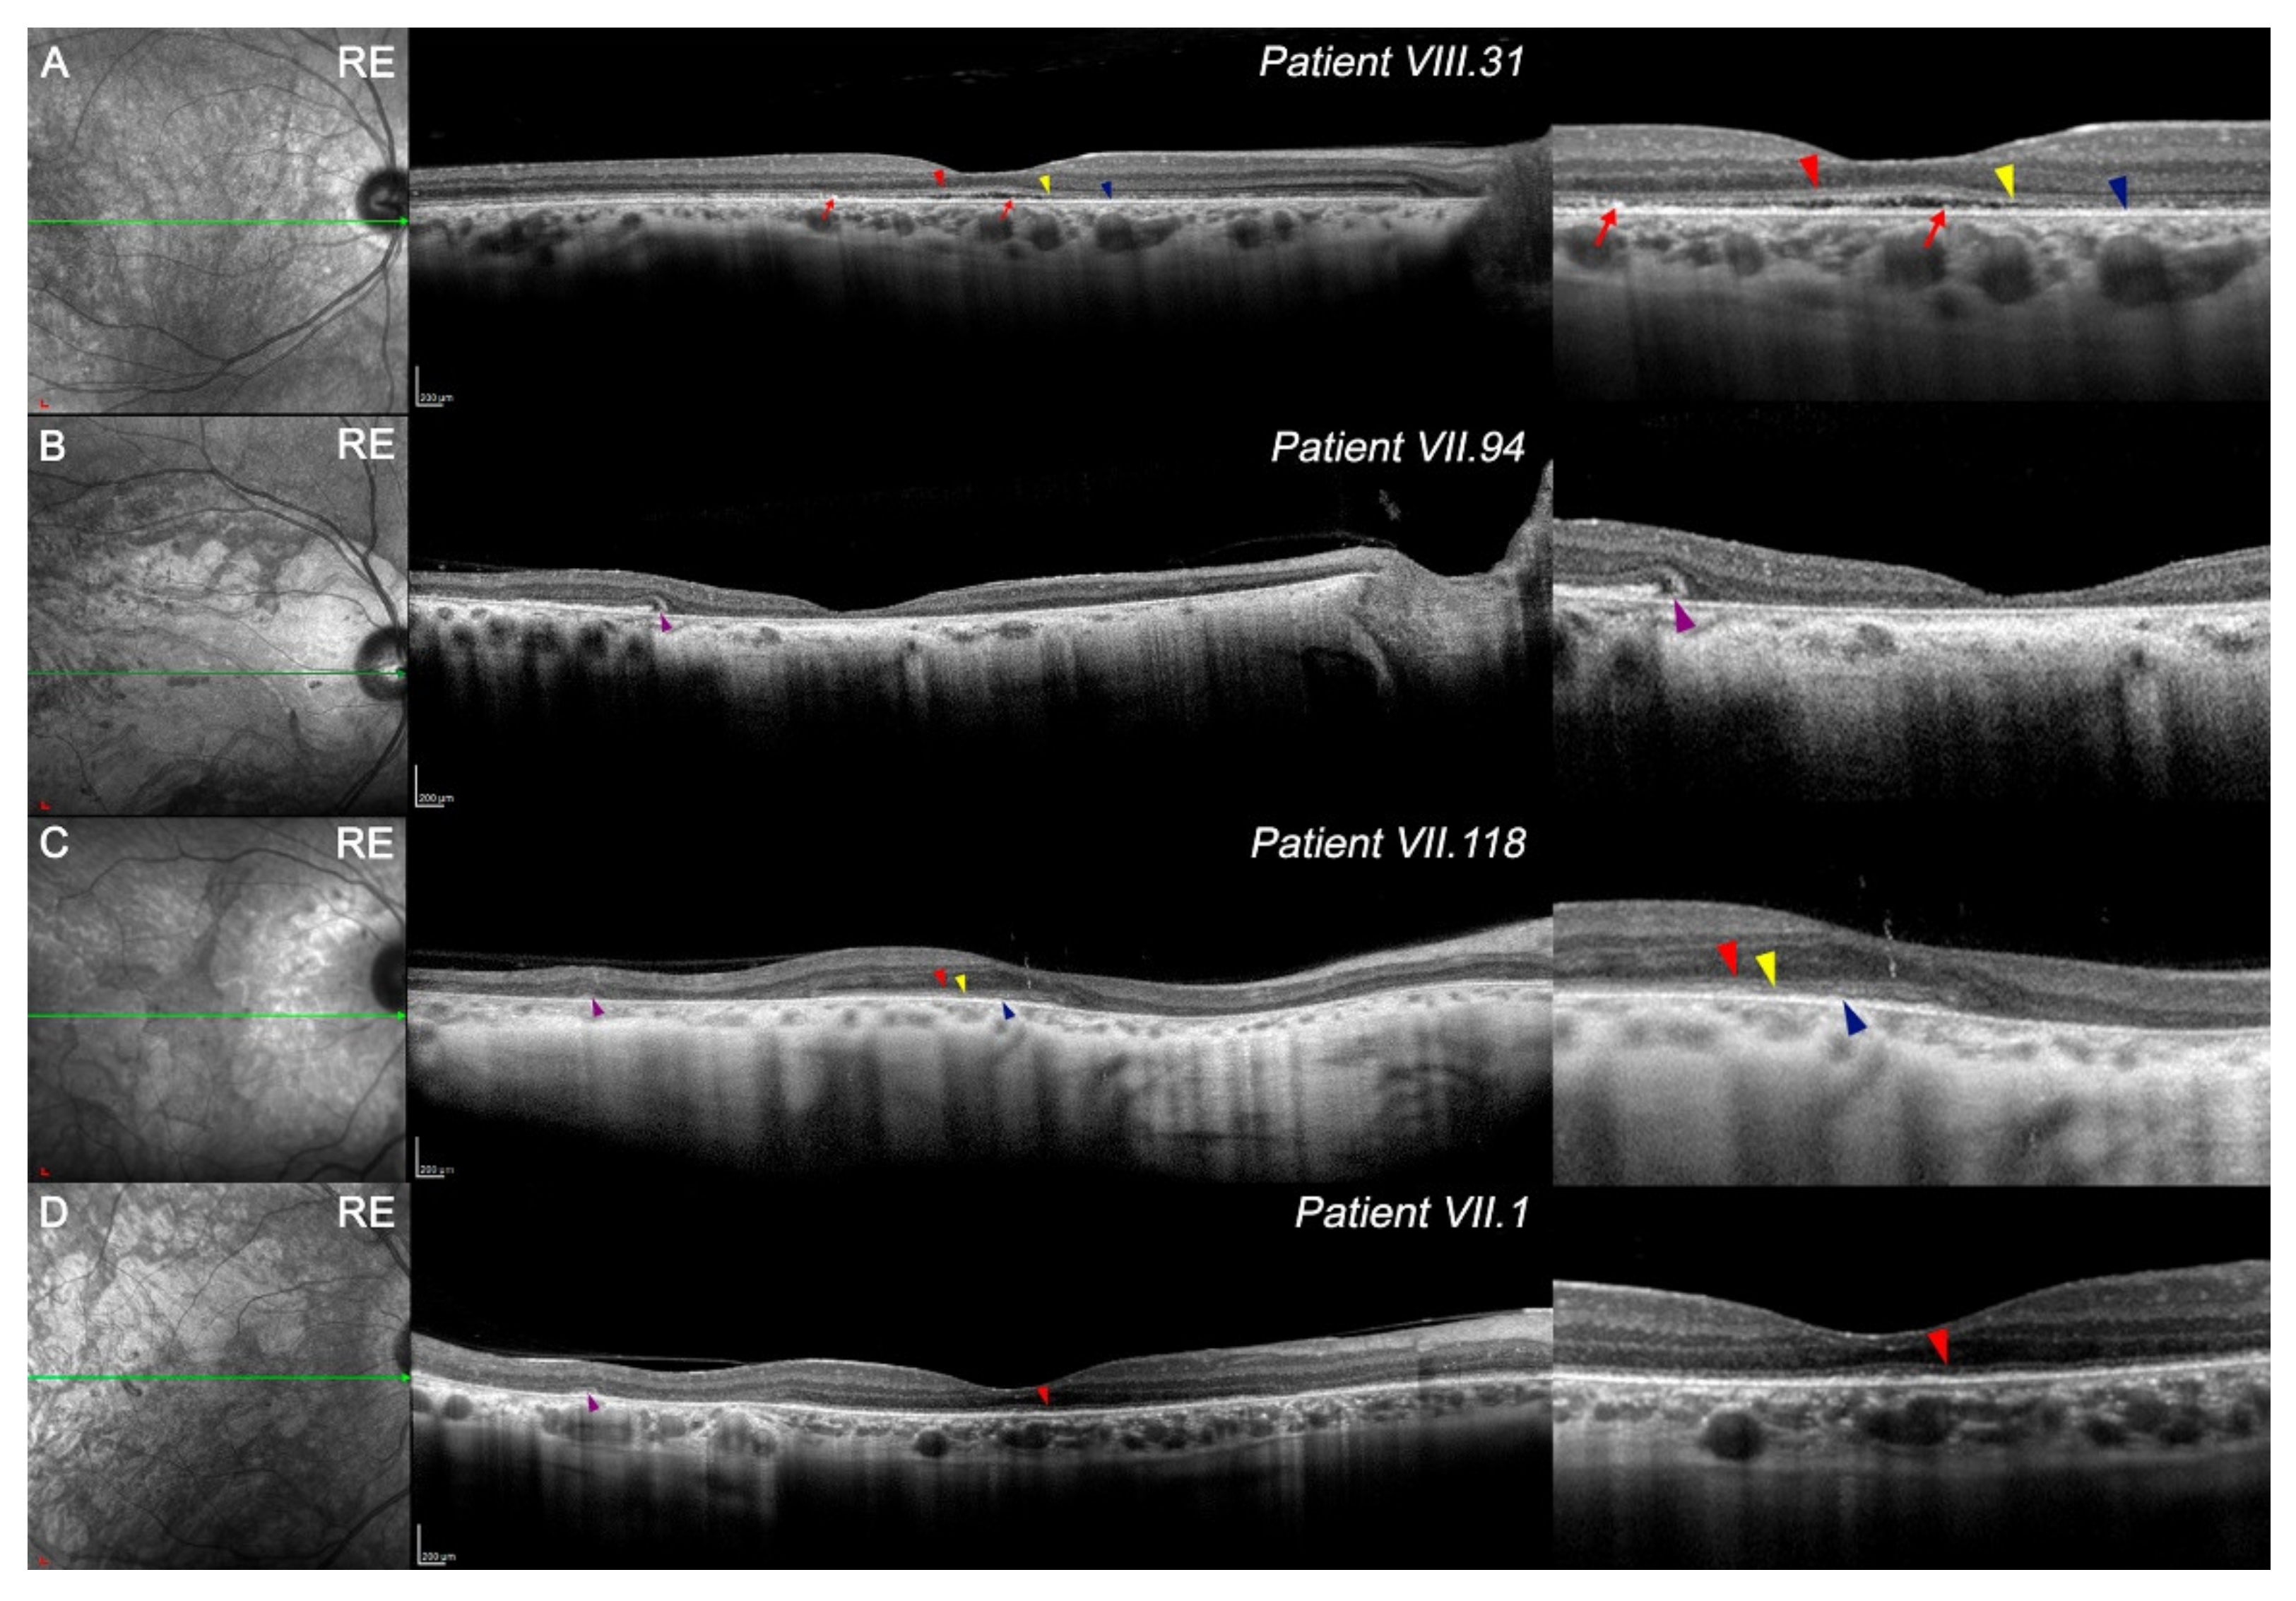

Figure 2.

IR images (left) and OCT line scan at the foveola (right) in study patients. Right-side insets of all images show different signs in high magnification. (A) The retinal structure of patient VIII.31 is maintained, although a general thinning exists along the fovea, mainly on the temporal side. First (red arrowhead), second (yellow arrowhead), and fourth (blue arrowhead) outer retinal bands are preserved at some areas and some hyperreflective loci, which may be related to the third band (red arrows). (B) Patient VII.94 presented almost complete degeneration along the retina, specifically at the fovea, and outer tubulations can be observed (purple arrowhead). Part of the outer nuclear layer remained on the most temporal side. (C) Patient VII.118 showed a nasal and temporal reduction in thickness. Some outer retinal bands were observed at the fovea (red, yellow, and blue arrowheads), and outer tubulations related to this degenerative process can be also seen on the temporal side (purple arrowheads). (D) Patient VII.1 exhibited a marked reduction in the outer nuclear layer and only the first outer band is shown at the fovea (red arrowhead). Various outer tubulations were presented (purple arrowheads). Scale A–D: 200x 200 um. Images of contralateral eye presented a similar degeneration pattern, though are not shown. Red arrowhead, first outer retinal band; yellow arrowhead, second band; blue arrowhead, fourth band; red arrow, hyperreflective loci from band 3; purple arrowheads, outer tubulations.

Regarding the four outer retinal bands, only VIII.31 (Figure 2A) showed a slightly preserved external limiting membrane (ELM; red arrowhead), cone ellipsoid zone (EZ; yellow arrowhead), and the fourth band (RPEmitZ; blue arrowhead) at the foveola. As a foveal cavitation existed, the third band (OS tips phagocytosed by the RPE, PhaZ) was disrupted. Some hyperreflective loci could be related to the remnants of the third band (Figure 2A, red arrows). To a lesser extent, the first, second, and fourth outer retinal bands were relatively maintained at the foveola in VII.118 (Figure 2C, red, yellow, and blue arrowheads, respectively). Otherwise, the first outer band was still observed in some parts of the foveola in VII.1 (Figure 2D, red arrowheads). Some outer retinal tubulations were observed in VII.94, VII.118, and VII.1 (Figure 2B–D, purple arrowheads).

The outer retinal layers from FAZ limits in the four members were reduced compared with healthy controls (Table 2); however, differences in retinal degeneration were found among them. Although VIII.31 still had homogeneous degeneration throughout the retina (Figure 2, Table 2), the OCT images of VII.94 showed a more aggressive thinning between the foveola and parafoveal limits (Figure 2B, Table 2). In VII.118 and VII.1, perifoveal thinning of the outer retina seemed to be more pronounced than in the parafovea (Figure 2C,D, Table 2). The high signal transmission on OCT, observed mainly in patient VII.94 (Figure 2C,D), may imply a greater degeneration of the RPE.

The structure and organization of the inner retina was maintained (Figure 2), though its thickness was usually reduced compared with healthy patients (Table 2). Foveal and parafoveal degeneration of these layers was greater in VIII.31 and VII.94 than in VII.118 and VII.1 (Table 2). Most areas of the inner retina of VII.1 exceeded the retinal thickness of control patients. Ganglion cell layer (GCL) distribution can be observed in Figure S4.